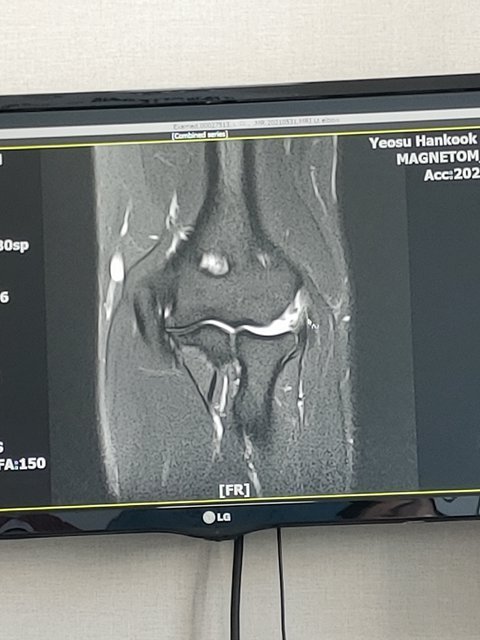

제가 사는 지역은 큰 병원이 없어 이송된 병원에서 치료가 불가하다 판단되어 다른 지역의 대학병원으로 이송되어왔고, 의사선생님은 저에게, 왼쪽 갈비뼈가 모두 부러짐과 동시에 비장이 파열 되었고, 오른쪽 무릎 파열, 왼쪽 팔 인대 끊어짐, 또 척추가 일부 손상되었지만 사고나실 때 몸을 웅크리고 계셨는지 신경은 살아있어서 다행히 걸을 수 있다고 무시무시한 말씀들을 덤덤하고 희망차게 전해주셨습니다. 오랜 재활이 필요하겠지만 오토바이 그것도 음주운전자가 낸 사고에 이정도면 죽지 않는걸 다행으로 생각하셔야 한다는 말씀과 함께요.

전치 12주 진단, 무릎은 평생 장해, 팔과 갈비뼈 등은 후유장해 5년 진단을 받고 8개월의 병원생활 끝에 통원이 가능해졌어도, 먹고 사는 문제가 기다리고 있었습니다. 제가 병원에 있는 동안 거래처들은 이미 다 떠나간 뒤였고, 코로나의 타격에도 어떻게든 악착같이 버텨보던 아내의 카페는 제 병간호로 인해 폐업을 하게 되었습니다.